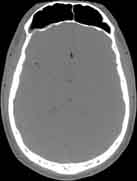

Visible Human male: Sectio transversalis 1084

CT